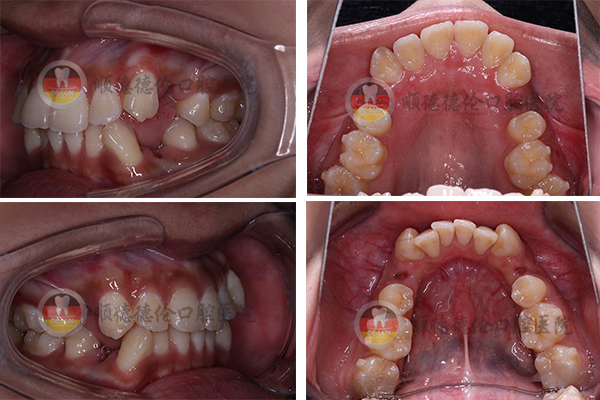

牙齒狀況:牙齒外突、擁擠、不整齊

3、拍口內照

上下兩排牙齒共拔了8顆牙齒,為了變美我也是拼了(⊙o⊙)

我的方案是要拔牙的,說出來估計會嚇到別人,因為我拔了8顆,分三次拔完了,估計很少有人能夠理解,周圍不少朋友說我瘋了,我是想美想瘋了,哈哈哈……